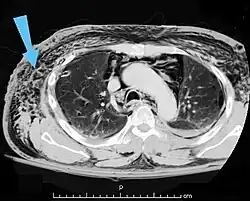

Verletzungen der Lunge können neben einer Lungenkontusion als Quetschverletzung Lungenrisse sein. Letztere führen zu einem Pneumothorax, wie er bei 10 bis 50 Prozent der Patienten mit Thoraxtrauma auftritt,[6] und gegebenenfalls zu einem Spannungspneumothorax. Blutungen in den Thorax hinein führen zu einem Hämatothorax. Bei einem Hämatopneumothorax treten sowohl ein Pneumo- als auch ein Hämatothorax in Kombination auf. Symptome sind zunächst Luftnot und je nach Ausmaß der Blutung auch Kreislaufinstabilität. Bei einem Pneumothorax kann sich insbesondere bei Ausbildung eines Spannungspneumothorax ein Hautemphysem bilden, das eine große Ausdehnung erreichen kann. Therapie ist eine Entlastung der Pleurahöhle mittels Thoraxdrainage auf der betroffenen Seite. Üblicherweise kommen kleinere intrathorakale Blutungen von alleine zum Stehen, so dass außer einer Drainage keine weiteren Maßnahmen notwendig werden. Eine Thorakotomie zur operativen Blutstillung kann bei einem initialen Blutverlust von mehr als 1.500 ml nach der Thoraxdrainage oder bei einem fortwährenden Blutverlust von mehr als 250 ml pro Stunde über mehr als vier Stunden erfolgen.[2][5]

Thorako-abdominelle Verletzungen

Die Kombinationsverletzung von Thorax und Abdomen ist die vierthäufigste Kombination bei mehrfachverletzten Patienten.[2] Insbesondere Zwerchfell, Leber und Milz sind auch bei isolierten Thoraxtraumen oft mitbetroffen. So können beim stumpfen Thoraxtrauma gebrochene Rippen in Leber oder Milz spießen und starke Blutungen verursachen. Durch ein plötzliches Kompressionsereignis kann das Zwerchfell ein- oder beidseits rupturieren und es kann zur Verlagerung von Bauchorganen in den Brustkorb kommen. Hierbei kommt es zu einer mechanischen Kompression der Lungen mit Luftnot und abgeschwächtem Atemgeräusch auf der betroffenen Seite. Bei einer rechtsseitigen Zwerchfellruptur liegt mit sehr großer Wahrscheinlichkeit auch eine schwere Verletzung der Leber vor.[2] Bei penetrierenden Thoraxtraumen können die in den Körper eindringenden Fremdkörper wie Projektile oder Messer sich bis in den Bauchraum bewegen und dortige Organe mitverletzen.[2] Symptome von intraabdominellen Organverletzungen sind Schock und Anzeichen eines akuten Abdomens.[2]